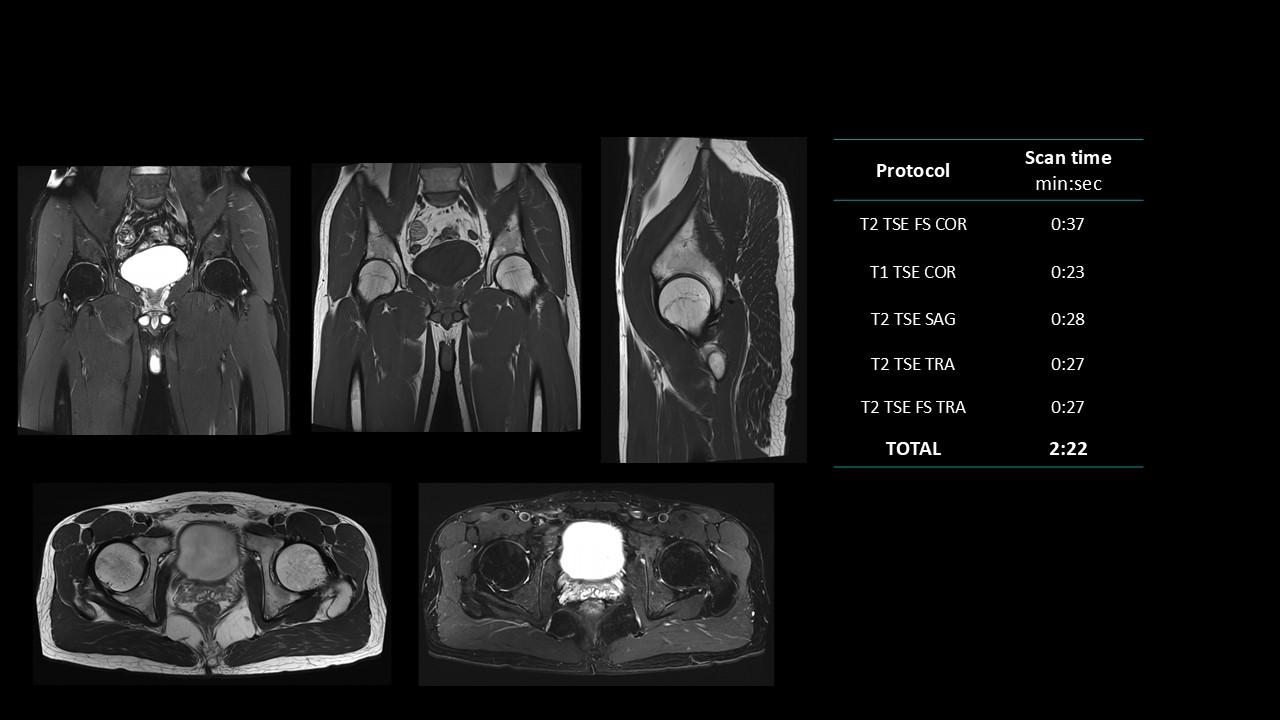

The Deep Resolve protocols are a set of advanced 3T MR imaging protocols designed to achieve high-quality diagnostic imaging with significantly reduced acquisition times.

Enabled by Deep Resolve, the AI-powered image reconstruction technology, these protocols deliver high-quality scans in approximately three minutes across a wide range of anatomical regions.

Developed and meticulously evaluated by Dr. Seong-ho Lee of Leaders Radiology Hospital in Seoul, Korea, the protocols integrate deep learning technology to enhance imaging efficiency while maintaining diagnostic detail.

By reducing scan duration, they improve workflow efficiency and patient experience without compromising image quality.